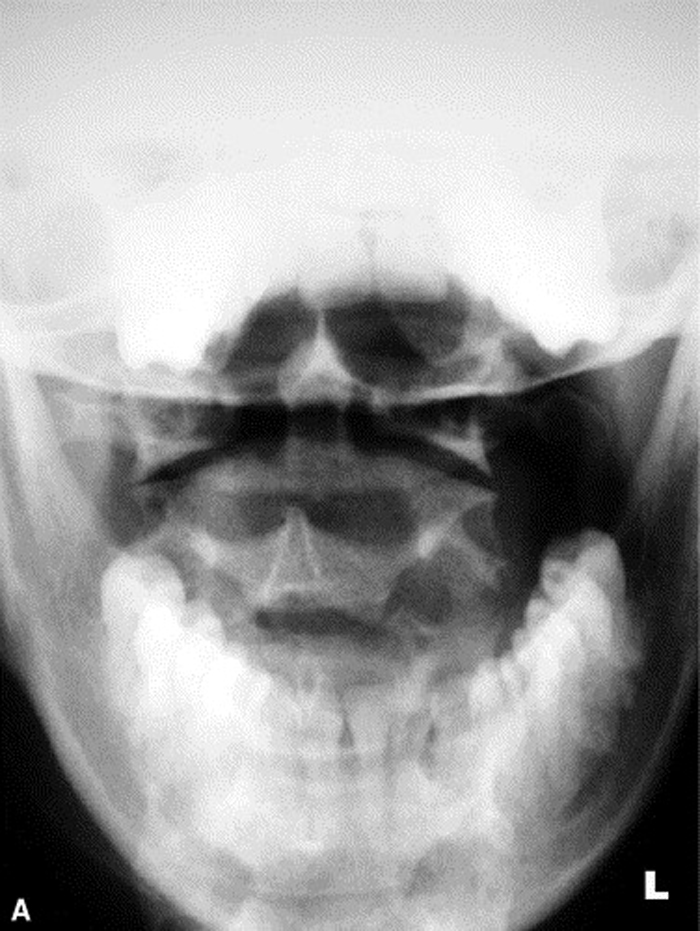

Radiographs were ordered (Figure 1, A through C) due to the longevity of the complaint and revealed a persistent narrowing of the left para-odontoid space. The radiology report stated that the asymmetry might be due to a right rotational malposition of atlas, possibly a compensatory response to a left rotational fixation of axis.

Figure 1.

A: Neutral and angulated anteroposterior open month

radiographs reveal a narrowed left para-odontoid space.